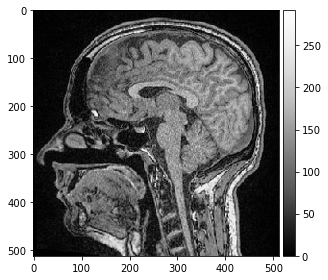

image = imread('../../data/Haase_MRT_tfl3d1.tif')

imshow(image[100])